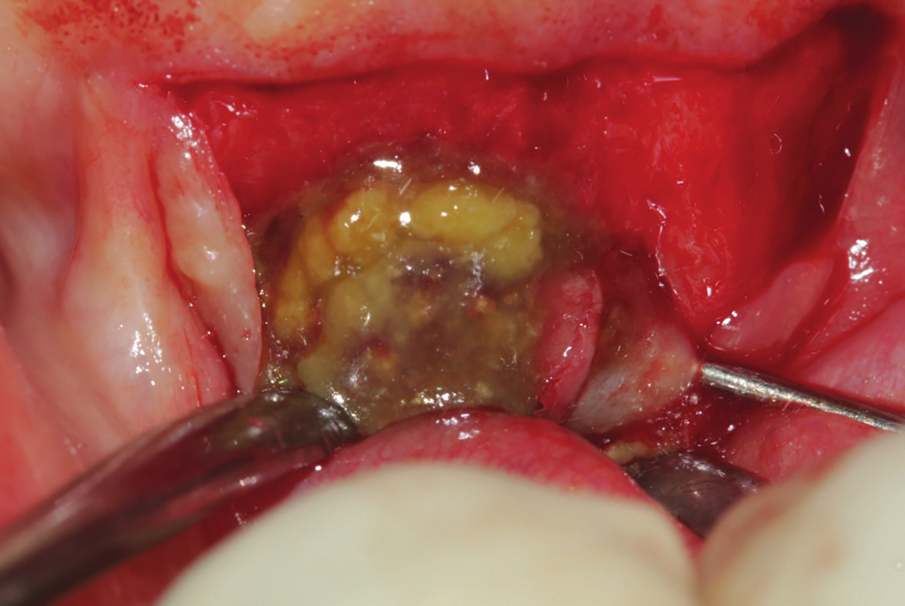

Figure 24: Bone cavity showing extended bone loss.

Figure 25: 3 months post-operative intervention, showing extended bone loss in the area.

A 38 years-old female patient came to our clinic with swelling upper anterior area, she was medically fit with no health problems. The patient underwent an orthodontic treatment for 2 years and was about to remove it and place retainer. Intraoral examination showed swelling apical area of tooth no 7. The periapical x-ray and CAT view revealed a lateral perforation on the same mentioned tooth with a well circumscribed radiolucency in apical area (Fig.20, 21). Pain on percussion and slight mobility were noted. A surgical enucleation and extraction of tooth no 7 were conducted (Fig.22, 23, 24). 3 months postoperative CAT view shows an advanced horizontal bone loss with no recurrence of lesion in the area (Fig. 26), clinically after reflection of mucoperiosteal flap, the situation confirmed the CAT image (Fig.25) , the case was planned for PRF -associated bovine bone technique replacing the aggressive autologous bone graft procedure. After collection of PRF from patient blood culture, a first layer of L-PRF covering the bovine bone associated PRF complex (sticky bone) was done (Fig.27). The second layer of L-PRF came to cover the cross-linked collagen membrane (Fig. 28).